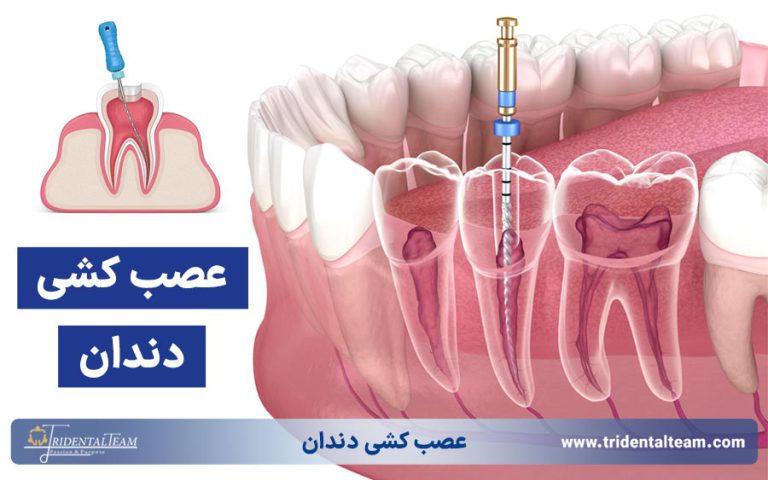

- عصب کشی دندان: درمان ریشه دندان آسیب دیده برای رفع درد و حفظ دندان.